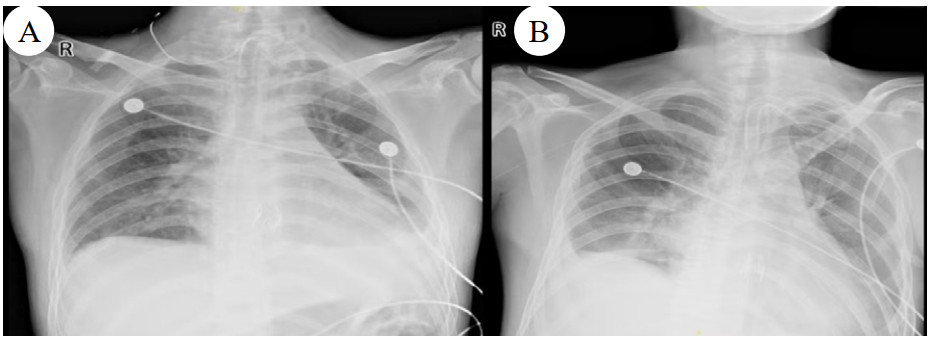

同时给予镇痛、镇静联合肌松,去甲肾上腺素泵入维持血压,俯卧位通气,B某入院后出现高热,经验性给予美罗培南联合万古霉素抗感染治疗,后降阶梯调整为哌拉西林他唑巴坦联合万古霉素治疗;C某抗感染方案为经验性使用万古霉素联合哌拉西林他唑巴坦治疗,痰培养出鲍曼不动杆菌后改为替加环素、头孢哌酮舒巴坦及万古霉素治疗;根据《刺激性气体中毒诊治专家共识》[5]中关于重症患者的治疗措施,同时给予2人泮托拉唑抑酸护胃,氨溴索、富露施化痰、甲泼尼龙抗炎、西维来司他纳及乌司他丁清除炎性介质,维生素C抗氧化、保肝、输血补液,纤支镜吸痰及肺泡灌洗,维持水电解质平衡及营养支持治疗,特别考虑到肺损伤情况,在使用有创通气时给予超保护性通气策略[5, 7];2人仍先后出现气胸、纵膈气肿,行胸腔闭式引流;持续V-V ECMO治疗15 d后,肺部纤维化不可逆转,高分辨率CT肺纤维化评分 > 75%(图 3、4),符合终末期肺病标准,有肺移植指征[8],经评估后2人顺利完成病变肺组织切除(图 5),双侧序贯肺移植,术后患者复查胸片肺部恢复正常(图 6),2位患者术后气管切管接呼吸机辅助通气,并给予泼尼松、他克莫司、吗替麦考酚酯抗排异治疗,其余根据病情给予万古霉素调节肠道菌群、抗感染、保肝、抗凝、呼吸康复锻炼等治疗,后顺利脱机、拔除气切套管,病情稳定出院,后续规律复查胸部CT(图 7)恢复良好。

| 注:图A为B某;图B为C某 图 6 患者肺移植术后胸片 |

| 注:图A为B某;图B为C某 图 7 肺移植术后第2个月、5个月、8个月CT影像 |